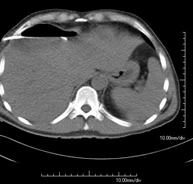

Prova diagnòstica que consisteix en l'estudi de l'abdomen d'alta definició anatòmica (fetge, vesícula biliar, via biliar, pàncrees, melsa, estómac, intestins, ronyons, estructures vasculars, bufeta, úter i ovaris, etc.) mitjançant l'ús d'un equip de TC (Tomografia Computeritzada). Aquestes imatges s'estudien posteriorment en una estació de treball que permet obtenir reconstruccions bidimensionals en diferents plànols de l'espai i també reconstruccions 3D (volumètriques). La majoria d'estudis requereixen l'ús de contrast iodat per millorar la definició de les imatges. - TC Pelvis

Prova diagnòstica que consisteix en obtenir imatges bi i tridimensionals de l'abdomen d'alta definició anatòmica (estructures òssies, estructures vasculars, fetge, pàncrees, vesícula biliar, ronyons, glàndules suprarenals, melsa, intestí prim i gros, bufeta, úter i ovaris, pròstata i vesícules seminals, urèters, etc.) mitjançant l'ús d'un equip de TC (Tomografia Computeritzada). La majoria d'estudis requereixen l'ús de contrast iodat. - TC Fetge

Prova diagnòstica que consisteix en obtenir imatges bi i tridimensionals del fetge d'alta definició anatòmica mitjançant l'ús d'un equip de TC (Tomografia Computeritzada). És necessari realitzar l'estudi abans i després de l'ús de contrast iodat, i realitzar l'estudi en diferents "fases hepàtiques" per valorar correctament totes les estructures: parènquima hepàtic, via biliar intra i extrahepàtic, vesícula biliar, vasos hepàtics (artèria hepàtica, vena porta i venes suprahepàtiques) i estructures adjacents (estómac, duodè, vena cava inferior, glàndula pancreàtica, etc.). Aquesta prova està especialment indicada en l'estudi de lesions hepàtiques, estudi d'hepatopaties cròniques, etc. - TC Ronyons